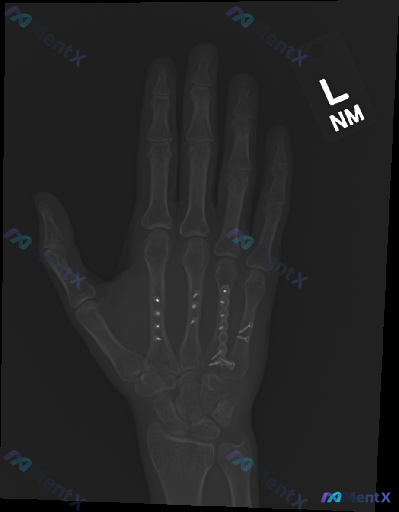

这是一个左手掌骨术后复查的影像学病例讨论。X光片显示第3、4、5掌骨存在金属内固定物,骨痂生长尚可;但围绕内固定系统的稳定性、是否存在隐匿风险,有多个观察与判断方向值得梳理。